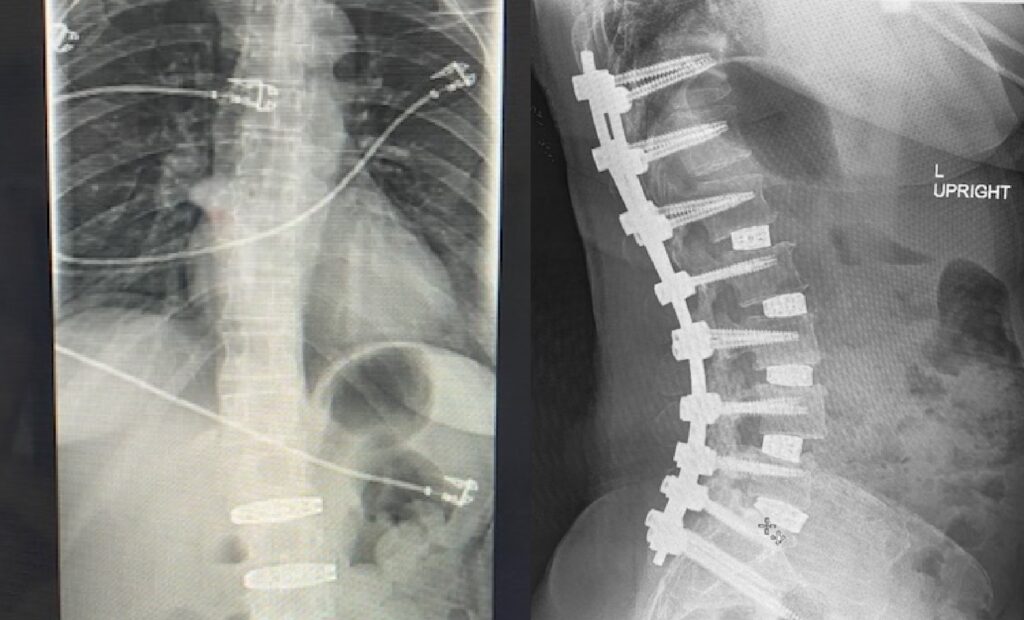

MISS scoliosis correction using 3 small incisions for reduced tissue disruption and faster recovery. Read Case Study

A proven surgical solution that stabilizes the spine, relieving pain and improving structural support with minimal disruption.